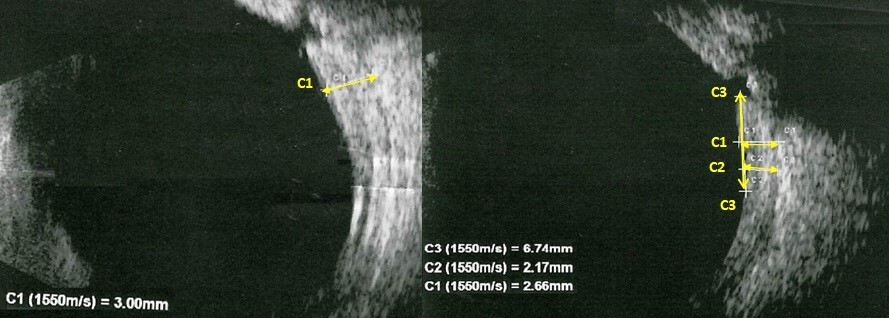

РЕЗУЛЬТАТЫ. На первые сутки после операции на левом глазу выявлено: гипотония, измельчение передней камеры, серозная цилиохориоидальная отслойка. Проведена задняя трепанация склеры, восстановлен объем передней камеры вискоэластиком. На следующие сутки нормализация ВГД и полное прилегание сосудистой оболочки, но обнаружена отслойка нейроэпителия в макулярной области, в связи назначены инъекции глюкокортикостероидов с положительным эффектом. Через 1 месяц после операции жалобы отсутствуют, оболочки прилежат, на левом глазу ВГД - 16 мм рт. ст. без гипотензивных капель, острота зрения на оба глаза 1,0.